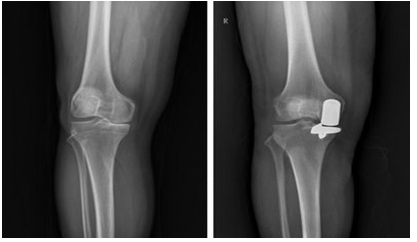

“我还年轻,有没有更加创伤小、恢复快的手术选择?”带着这个疑问,李长荣辗转来到燕达医院。刘清和主任对其进行全面评估后,认为患者较年轻,膝内翻伴关节内侧间室单室病变,特别适合行膝关节单髁置换手术。

手术当天先由刘清和主任主刀,手术切口仅有7cm,而全膝关节切口通常为15cm,甚至更长;截骨创伤为全膝关节置换术的1/3;术中出血量很少,无需放置引流。整个手术时间仅为半小时。患者术后1小时便可进行主动康复训练,术后第1天便可下地行走,术后1周满足了心愿的李长荣顺利出院返家休养。解决了困扰老李多年的膝关节疼痛,达到了快速康复效果。如此之快的康复速度,全膝关节置换是无法做到的。